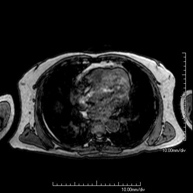

- Tòrax

- RM del Mediastí

Prova diagnòstica no invasiva que consisteix en l'obtenció d'imatges d'alta definició anatòmica del mediastí mitjançant l'ús d'un camp electromagnètic i ones de ràdio (amb un emissor i un receptor). No utilitza radiació ionitzant. El mediastí és la part central de la caixa toràcica que inclou el tim, els grans vasos (aorta toràcica, vena cava inferior i superior, etc.), el cor, la tràquea i els bronquis principals, els ganglis limfàtics mediastínics i hilars, l'esòfag, etc. Està especialment indicada en lesions mediastíniques per diferenciar si són quístiques o sòlides, en el diagnòstic diferencial de les lesions del mediastí anterior, etc. De vegades s'ha d'emprar contrast paramagnètic (Gadolini) per completar l'estudi. - RM Tòrax

Prova diagnòstica no invasiva que consisteix en l'obtenció d'imatges d'alta definició anatòmica del tòrax mitjançant l'ús d'un camp electromagnètic i ones de ràdio (amb un emissor i un receptor). No utilitza radiació ionitzant. Està indicada en aquelles lesions pulmonars en les quals s'ha de descartar si hi ha infiltració del mediastí o de la paret toràcica, per diferenciar si una lesió toràcica és sòlida o quística, etc. En alguns casos caldrà emprar contrast paramagnètic (Gadolini) per completar l'estudi. - RM de Paret Toràcica

Prova diagnòstica no invasiva que consisteix en l'obtenció d'imatges d'alta definició anatòmica de la paret toràcica mitjançant l'ús d'un camp electromagnètic i ones de ràdio (amb un emissor i un receptor). No utilitza radiació ionitzant. Està indicada en l'estudi de lesions de paret toràcica: costals, esternals, musculars (pectorals, intercostals, paravertebrals, etc.), en l'estudi de dolors costals, etc. En alguns casos caldrà emprar contrast paramagnètic (Gadolini) per completar l'estudi. - Angio-RM d'Aorta Toràcica